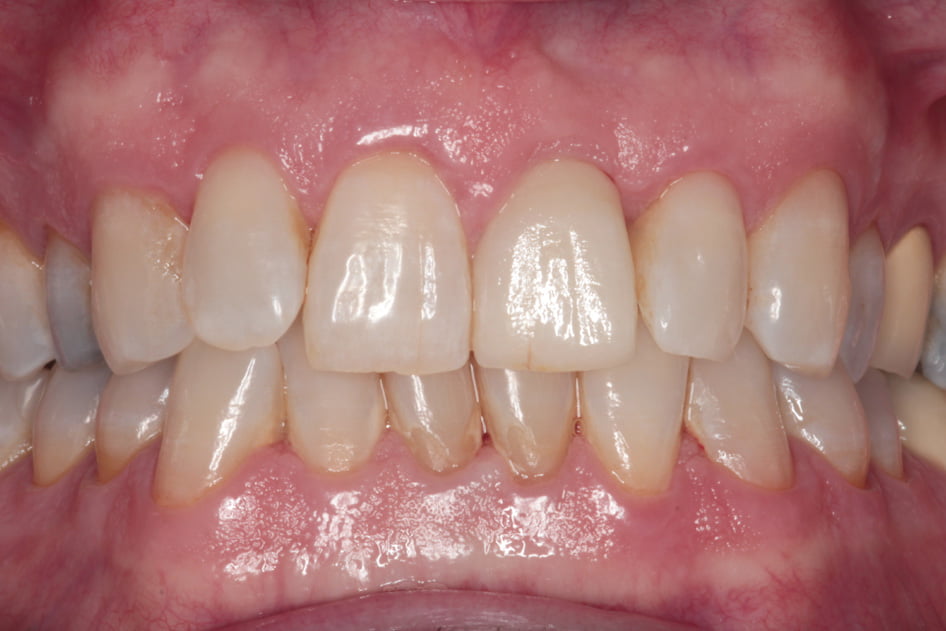

Gallery - Dental Implants

Case 2

Before After